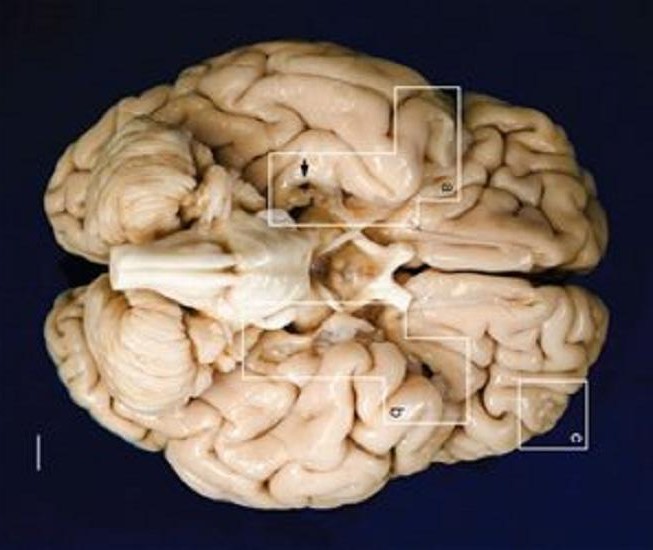

Ερευνητές του Πανεπιστημίου της Καλιφόρνια στο Σαν Ντιέγκο δημοσιεύουν τα αποτελέσματα της ανατομικής μελέτης στον διατηρημένο εγκέφαλο του H.M, τον οποίο έκοψαν έκοψαν σε 2.401 λεπτές φέτες προκειμένου να δημιουργήσουν ένα λεπτομερές τρισδιάστατο μοντέλο.

Ο Χένρι Γκούσταβ Μολέισον γεννήθηκε το 1926 και εμφάνισε σοβαρή επιληψία σε μικρή ηλικία. Το 1953 υποβλήθηκε σε επέμβαση από τον αμερικανό χειρουργό Ουίλιαμ Σκόβιλ, ο οποίος προχώρησε στην αφαίρεση αρκετών δομών του εγκεφάλου, ανάμεσά τους και οι δύο ιππόκαμποι.

Οι επιληπτικές κρίσεις εξαφανίστηκαν, όμως ο H.M. έχασε την ικανότητα να αποθηκεύει νέες αναμνήσεις. Η περίπτωση του προσέφερε τις πρώτες σαφείς ενδείξεις για τη λειτουργία του ιπποκάμπου, ο οποίος πιστεύεται σήμερα ότι συμμετέχει στην εδραίωση αναμνήσεων μέσω της μεταφοράς τους από τη βραχυπρόθεσμη στη μακροπρόθεσμη μνήμη.

Η οριστική απόδειξη έρχεται τώρα από την ανατομική μελέτη του Δρ Τζάκοπο Ανέσι στο Παρατηρητήριο Εγκεφάλου του Πανεπιστημίου της Καλιφόρνια στο Σαν Ντιέγκο. Το τρισδιάστατο μοντέλο που δημιούργησε δείχνει ότι ένα τμήμα του ιπποκάμπου έμενε ανέπαφο, είχε όμως αποσυνδεθεί από άλλες δομές που συμμετέχουν στην εδραίωση των αναμνήσεων.